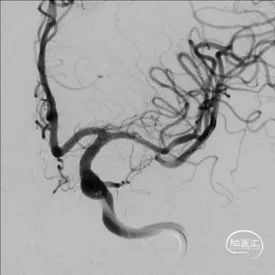

DSA

重要影像结论:左大脑中动脉M1末端重度狭窄。

扩张后造影

全脑及病变处不同体位造影:狭窄处成形好,未残余明显狭窄,左大脑中动脉主干及各分支显影好。